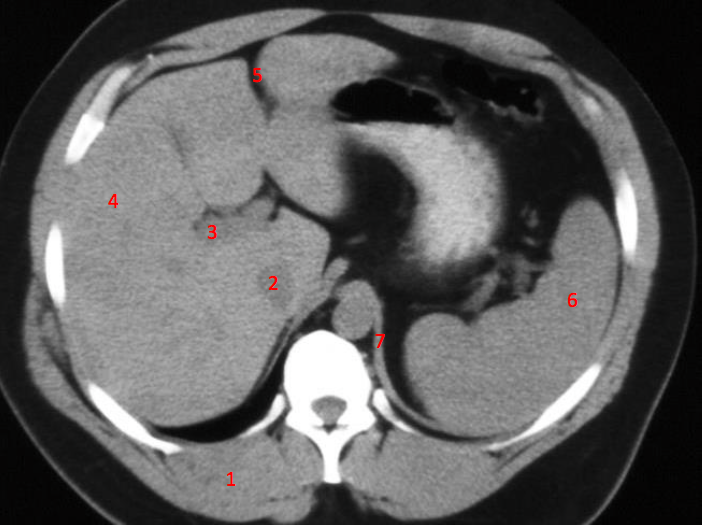

Number 1?

R lung

Number 2?

Rt lobe of liver

Number 6?

Stomach

Number 8?

Bladder